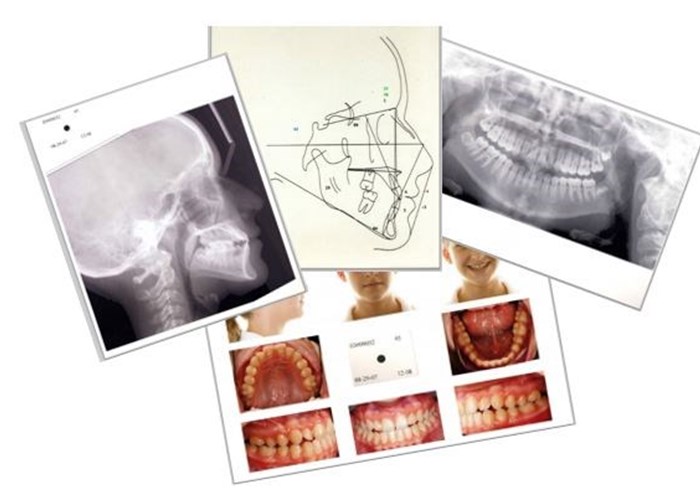

The examinee will provide case presentations that contain specific reports and patient records that are required by the Board. The patient records should be of sufficient quality and accuracy that an appropriate diagnosis and observation of treatment results may be adequately viewed by the examiner. The case will be evaluated for quality, accuracy and completeness of the patient records and reports in meeting ABO specifications.